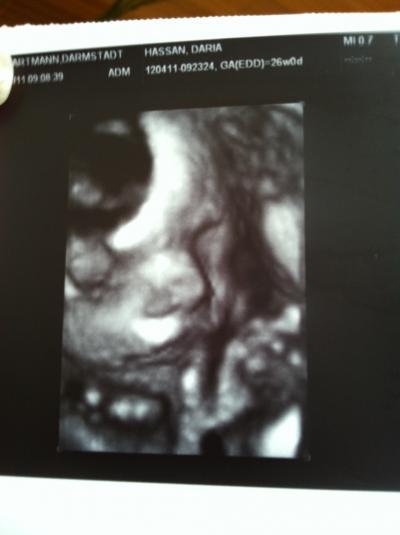

Huhuu Ihr Lieben, heute hatte ich wieder den heißersehnten FA-Termin mit US und Diabetes-Test. Gooott...das hat so lange gedauert. Ich durfte ja nichts essen und die Hitze hat mich richtig fertig gemacht. Da sitzt man drei Stunden im Wartezimmer, bekommt alle 60 min. einen Pieks und wartet und wartet . Habe aber kein Diabetes. Naja...das Schöne kam ja auch noch: Marlene ist nu stolze 35 cm groß und wiegt 900 Gramm. Also lang und dünn :-) Aber die Ärztin meinte, dass die Babies wohl erst in die Länge wachsen. Alles in Ordnung. Der US war wieder total schön. Sie hat sich fleißig bewegt, uns den erhobenen Zeigefinger gezeigt und Fruchtwasser geschluckt. Hach, ich kanns kaum erwarten, bis sie da ist Dann gabs noch ein 3d-Bildchen. Ist ja ganz schön schwer, einen guten Moment abzupassen, wenn Madame sich so viel bewegt. Heute ist ein schöner Tag... auch wenn ich kurz vorm Zusammenbrechen bin. Scheiss Hitze und auf der Arbeit keine Klima Liebe Grüße an euch alle!!!!

Bild zu Zurück vom FA und in der 27sten - Forum für Oktober - Mamis